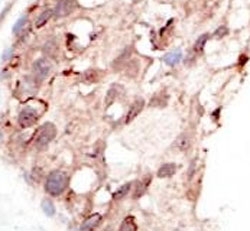

IHC analysis of FFPE human breast carcinoma tissue stained with the SUV39H2 antibody.

IHC (Paraffin) : 1:50-1:100